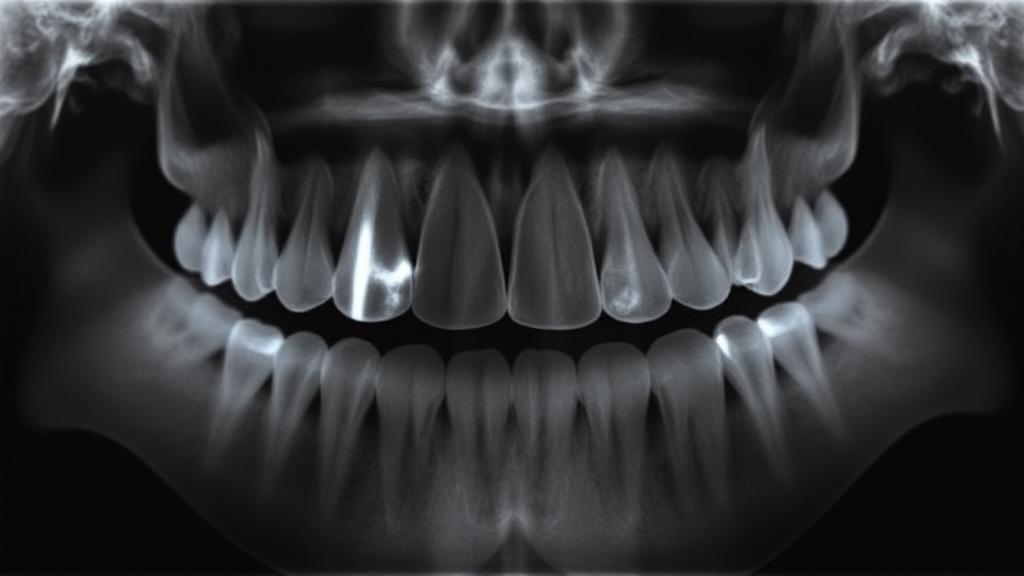

The Evaluation Process

Your dentist will typically use X-rays to assess your wisdom teeth's position and potential problems. The Mayo Clinic recommends regular dental check-ups during your teens and early 20s to monitor wisdom tooth development.